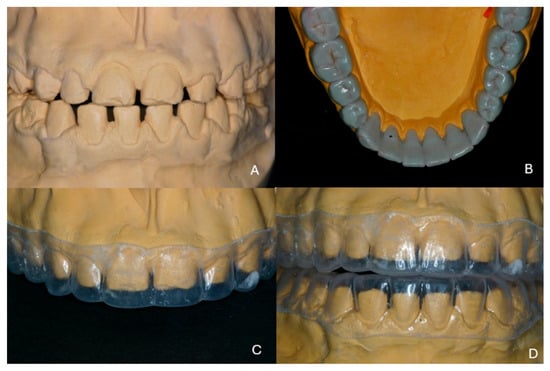

2. Case Presentation